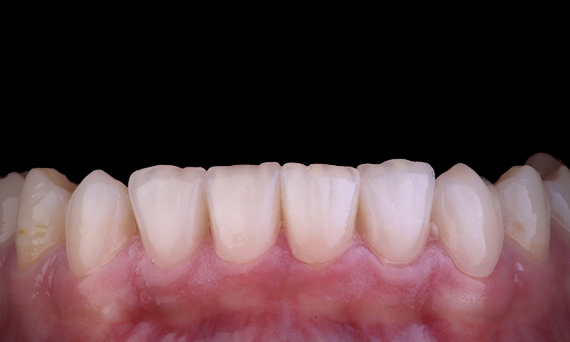

Avant : Situation clinique préopératoire. Traumatisme des incisives centrales maxillaires

Après : Restaurations collées.